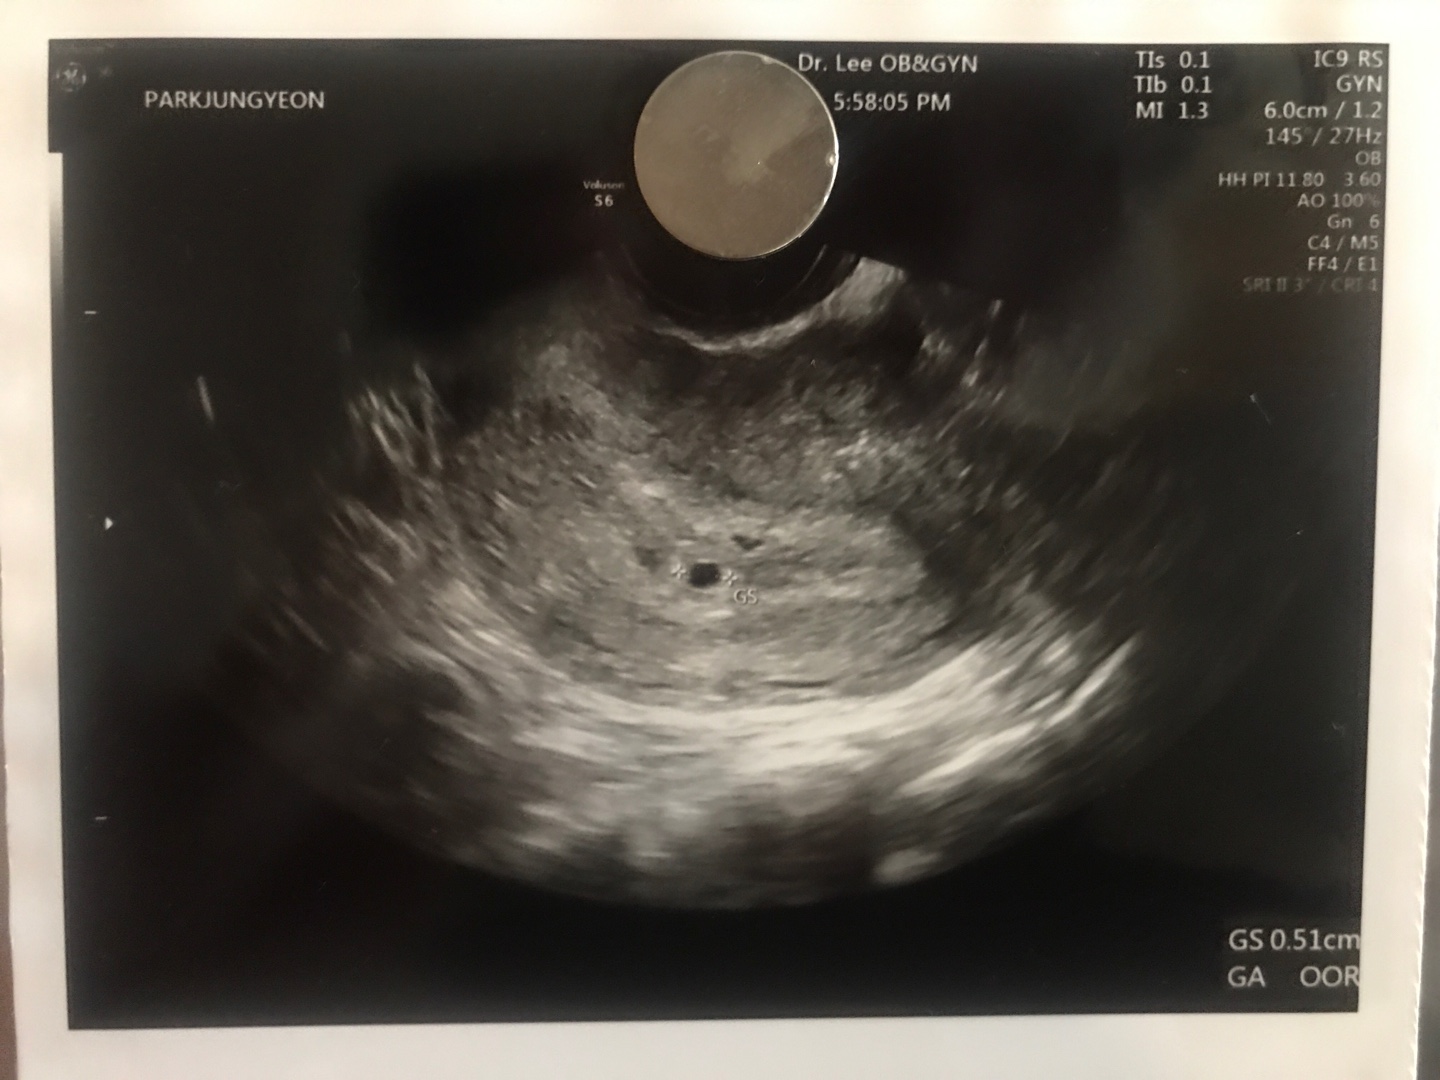

축하해 주세요! 여러분! 새로운 식구가 생겼습니다. 아들인지 딸인지 말랐는지 뚱뚱한지 키가큰지 작은지 똑똑한지 재주꾼인지 알 수는 없지만! 저 사진속 가운데에 있는 저 조그마한 녀석이 바로 피피의 새식구 '알콩이' 입니다.

알콩이는 현재 4-5주차로 뇌(Brain)를 만들고 있는 중이에요! 다음 주엔 아마도 심장과 위 등의 장기를 만들고 있을거에요. 1주일만에 사람의 형태를 띈다고 하니 정말 놀랍죠?

오늘은 보건소에 들려서 2달치 엽산과 임산부 뱃지, 초보 아빠 수첩, 음식안내문, 등 여러가지를 받았어요. 임신은 40주차 까지이고 현재 5주차 까지 왔습니다. 알콩이가 세상에 나오기 까지 앞으로 35주가 남았어요. 여러분도 알콩이의 미래 함께 응원해 주실꺼죠?